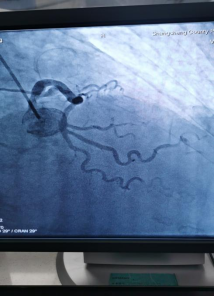

日前,商城县人民医院胸痛中心群里在半个小时内先后报告了两例来自李集乡的急性心梗患者,一场与时间赛跑,与死神博弈的生死急救快速拉开了帷幕!

急诊PCI对医院的硬件、人员配备等要求极高,能否开展急诊PCI目前已成为心血管领域彰显医院整体诊疗水平的标志。一台台成功的手术、一个个因救治及时而重获新生的患者,无不体现着我院胸痛中心日臻成熟的精确诊疗技术!也显示出我院在介入治疗领域已具备较强的综合实力。不论白昼还是黑夜、疾风或是暴雨,胸痛中心的电话就是命令!时间就是生命,时间就是心肌,胸痛中心团队始终秉持着生命至上、人民至上的理念,他们每天与时间赛跑,与死神搏斗!节省的每一分每一秒都在为急性心肌梗死患者争取生的希望,力求实现胸痛救治从急救到预防,从急病到慢病的延伸,随时待命为大别山区广大心血管疾病患者保“心”护航!